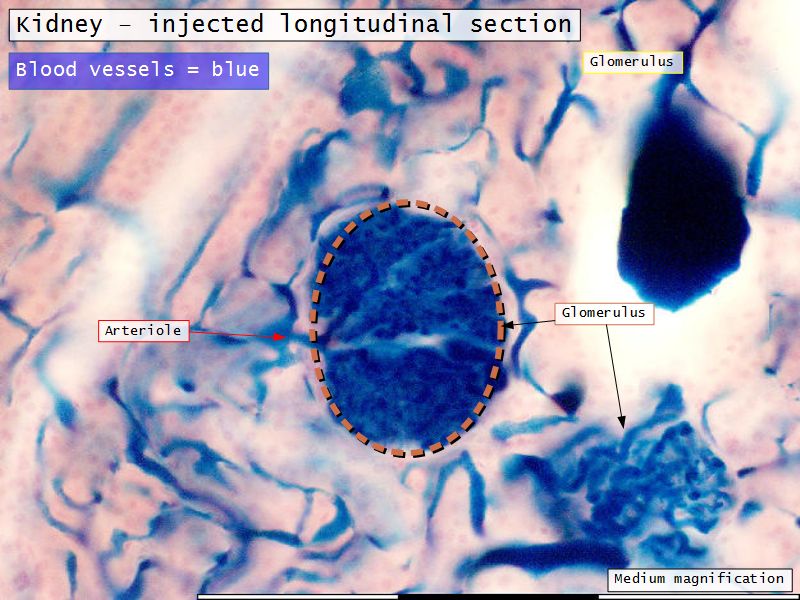

Renal corpuscle

- Tuft of capillaries

- grow into

- Blind end of nephron

- Several layers of epithelium

- Two sides

- Vascular pole

- Tubular pole

Blood flow

- Efferent arteriole

- Smooth muscle in media

- Capillaries

- Fenestrated

- Afferent arteriole

- Smooth muscle in media